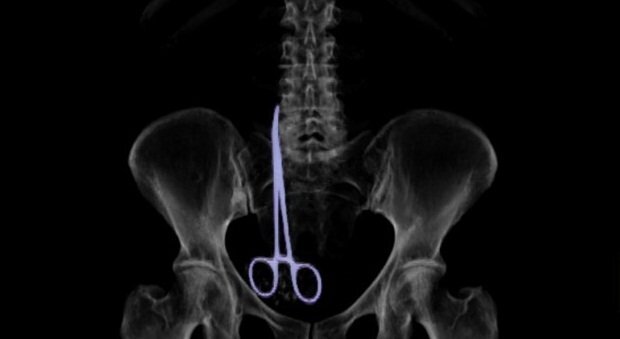

Bác sĩ để quên kéo dài 16cm trong cơ thể bệnh nhân suốt nửa năm

Bà Vera Petrova 63 tuổi (người Nga) liên tục phải chịu đau đớn sau ca phẫu thuật do chiếc kéo dài 16 cm nằm trong ổ bụng.